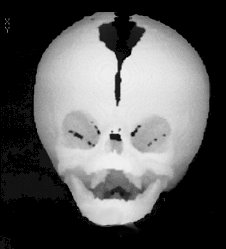

Metopic

• 4-10% of synostoses

• more common in males

• trigonocephaly (triangle-shaped head)

• recessed lateral orbital rim

• hypotelorism

• mild form: familial

• severe form: related to CNS dysmorphology